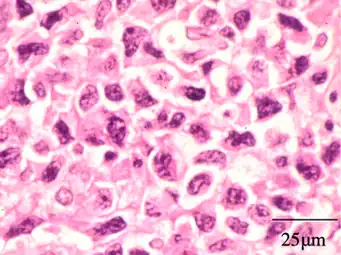

On histologic examination, nasal polyps consist of hyperplastic edematous (excess fluid) connective tissue with some seromucous glands and cells representing inflammation (mostly neutrophils and eosinophils). Polyps have virtually no neurons. Therefore, the tissue that makes up the polyp does not have any tissue sensation and the polyp itself will not be painful.[6] In early stages, the surface of the nasal polyp is covered by normal respiratory epithelium, but later it undergoes metaplastic change to squamous type epithelium with the constant irritation and inflammation. The submucosa shows large intercellular spaces filled with serous fluid.[15]

Benign mixed inflammation of an inflammatory nasal polyp.

Extranodal NK/T cell lymphoma, nasal type for comparison.[16] These lymphoma cells are typically monotonous, with folded nuclei, indistinct nucleoli and moderate amount of cytoplasm.[17]